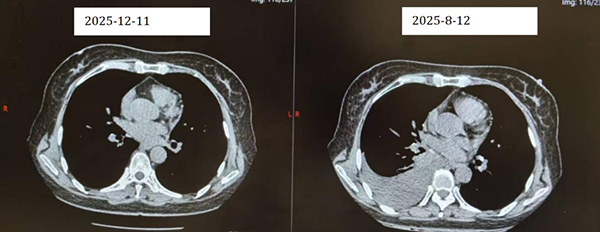

经过数月精心治疗,祝女士的复查结果令人振奋:影像学显示肿瘤明显缩小,达到部分缓解;头部MRI检查亦显示病情稳定。如今,她已能自由出行,重拾生活信心。“没想到,我还能像这样自由地旅行。”她笑着说——这笑容,正是对医疗团队最好的褒奖。